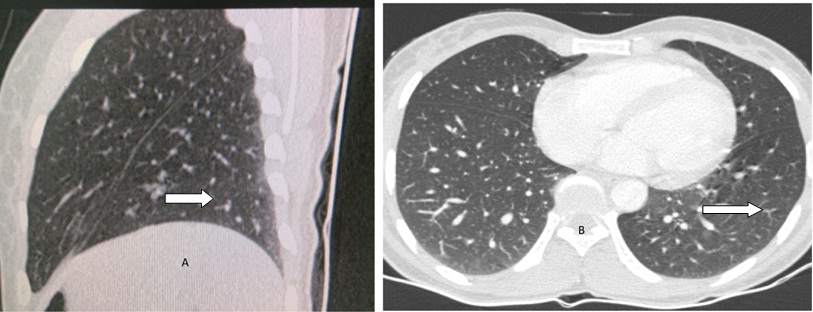

A 32-year-old female patient was admitted in pulmonary medicine ward with complaints of 20 episodes of haemoptysis since 11 months. She had no history of smoking and the tuberculosis work up by her treating physician was negative. Her clinical examination, blood picture and X-Ray chest PA view revealed no abnormality. She was referred to Department of Radiodiagnosis for HRCT Chest which revealed subtle area of ground glass haze in posterior basal segment of left lower lobe sub pleural in location [Table/Fig-1]. This HRCT was done when she was menstruating. On detailed clinical history the haemoptysis occurred during menstruation period with weakness and weight loss. Cough with expectoration of blood reoccurred every menstruation period lasting for few days. Total amount of blood expectorated as per patient’ s version was approximately 20-30 ml. She had history two normal vaginal deliveries and dilatation and curettage one year back for missed abortion. She gave no history of endometriosis. Ultrasonography of pelvis was normal. A repeat CT was done after control of haemoptysis and during non-menstruating period after 16 days of first CT. It showed complete resolution of the lesions [Table/Fig-2]. A diagnosis of thoracic endometriosis with catemenial haemoptysis was made. Bronchoscopy revealed hyperemic areas in left apicoposterior bronchus upper lobe and in right upper lobe apical segment bronchus. Bronchial washing was taken. Bronchial washing turned to be negative. Patient was put on tab Danazol 200 mg BD medical therapy, to which she responded well and suffered only one more minimal bout of haemoptysis. Monthly follow up visits were uneventful. Medication was discontinued after four months. After 8 months follow up the patient is clinically normal and had no fresh episodes of haemoptysis.

Axial and sagittal view showing clearing of the lesions (Arrows).

HRCT thorax is non-specific and may reveal ground glass or well-defined opacities, nodular lesions and thin-wall cavities [7] but it is the modality of choice for localization of endometrial deposits in the lung and pleura. In the presence of characteristic history and clinical examination, findings HRCT are considered diagnostic of pulmonary endometriosis [8]. Pleural lesions are usually right-sided, whereas lung lesions can be on either side [2]. This is explained by the fact that the lymphatic drainage is more extensive on right side of the diaphragmatic surface so embolic implant is more likely on right side [9]. HRCT chest in our patient revealed subtle area of ground glass haze in posterior basal segment of left lower lobe. This CT was taken during her menstrual period. Subsequent CT chest taken during non-menstruating phase showed complete resolution of the lesion. Serial HRCT findings along with the patient’s typical history were diagnostic of thoracic endometriosis.